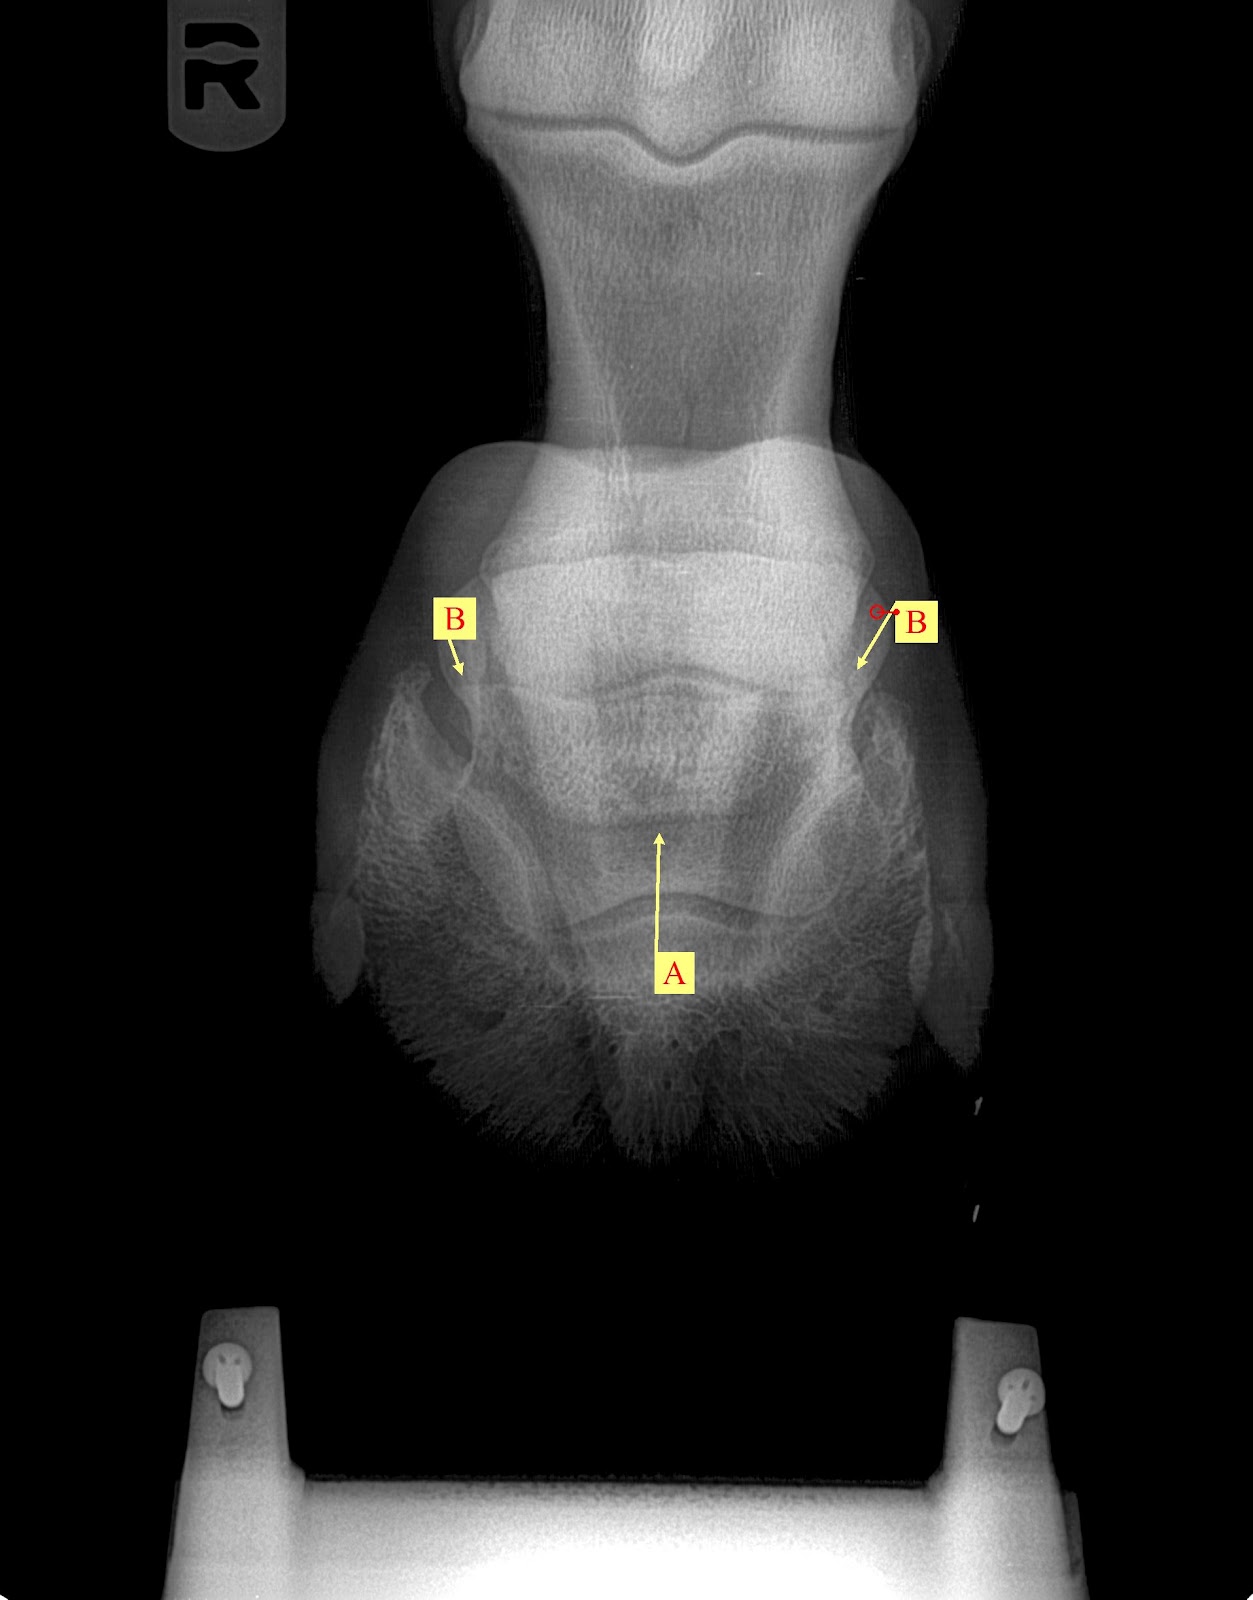

Horse Navicular X Ray . radiographs (x rays) are still important for examining the hoof’s bony structures and changes that are occurring. accurate radiographic evaluation of the navicular bone depends on a radiograph that is properly positioned and exposed and on a foot that is free of distracting artifacts. Many horses have pain in the heel region, which can be elicited by hoof testers. Radiographs will show any degenerative. However, researchers have found in. Abnormalities in the navicular bone navicular in horses relates to problems associated with the navicular bone in the horse’s hoof and is a common diagnosis for lameness in the front foot. Proper preparation for navicular radiography is similar to that for the distal phalanx, as discussed in chapter 23. a study looking at 72 horses that underwent mri for recent onset of navicular syndrome but without abnormalities detected on radiographs found the following: diagnostics involved in determining whether a horse has navicular syndrome include: Most horses show marked improvement in lameness with a palmar digital nerve block.

diagnostics involved in determining whether a horse has navicular syndrome include: radiographs (x rays) are still important for examining the hoof’s bony structures and changes that are occurring. navicular in horses relates to problems associated with the navicular bone in the horse’s hoof and is a common diagnosis for lameness in the front foot. Most horses show marked improvement in lameness with a palmar digital nerve block. Radiographs will show any degenerative. accurate radiographic evaluation of the navicular bone depends on a radiograph that is properly positioned and exposed and on a foot that is free of distracting artifacts. Abnormalities in the navicular bone Many horses have pain in the heel region, which can be elicited by hoof testers. However, researchers have found in. Proper preparation for navicular radiography is similar to that for the distal phalanx, as discussed in chapter 23.